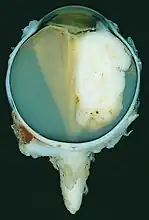

Gross and microscopic appearances of retinoblastoma are identical in both hereditary and sporadic types. Macroscopically, viable tumor cells are found near blood vessels, while zones of necrosis are found in relatively avascular areas. Microscopically, both undifferentiated and differentiated elements may be present. Undifferentiated elements appear as collections of small, round cells with hyperchromatic nuclei; differentiated elements include Flexner-Wintersteiner rosettes, Homer Wright rosettes,[25] and fleurettes from photoreceptor differentiation.[26]

Large exophytic white tumor with foci of calcification producing total exudative retinal detachment

A retinoblastoma as seen in an eye removed from a 3-year-old female